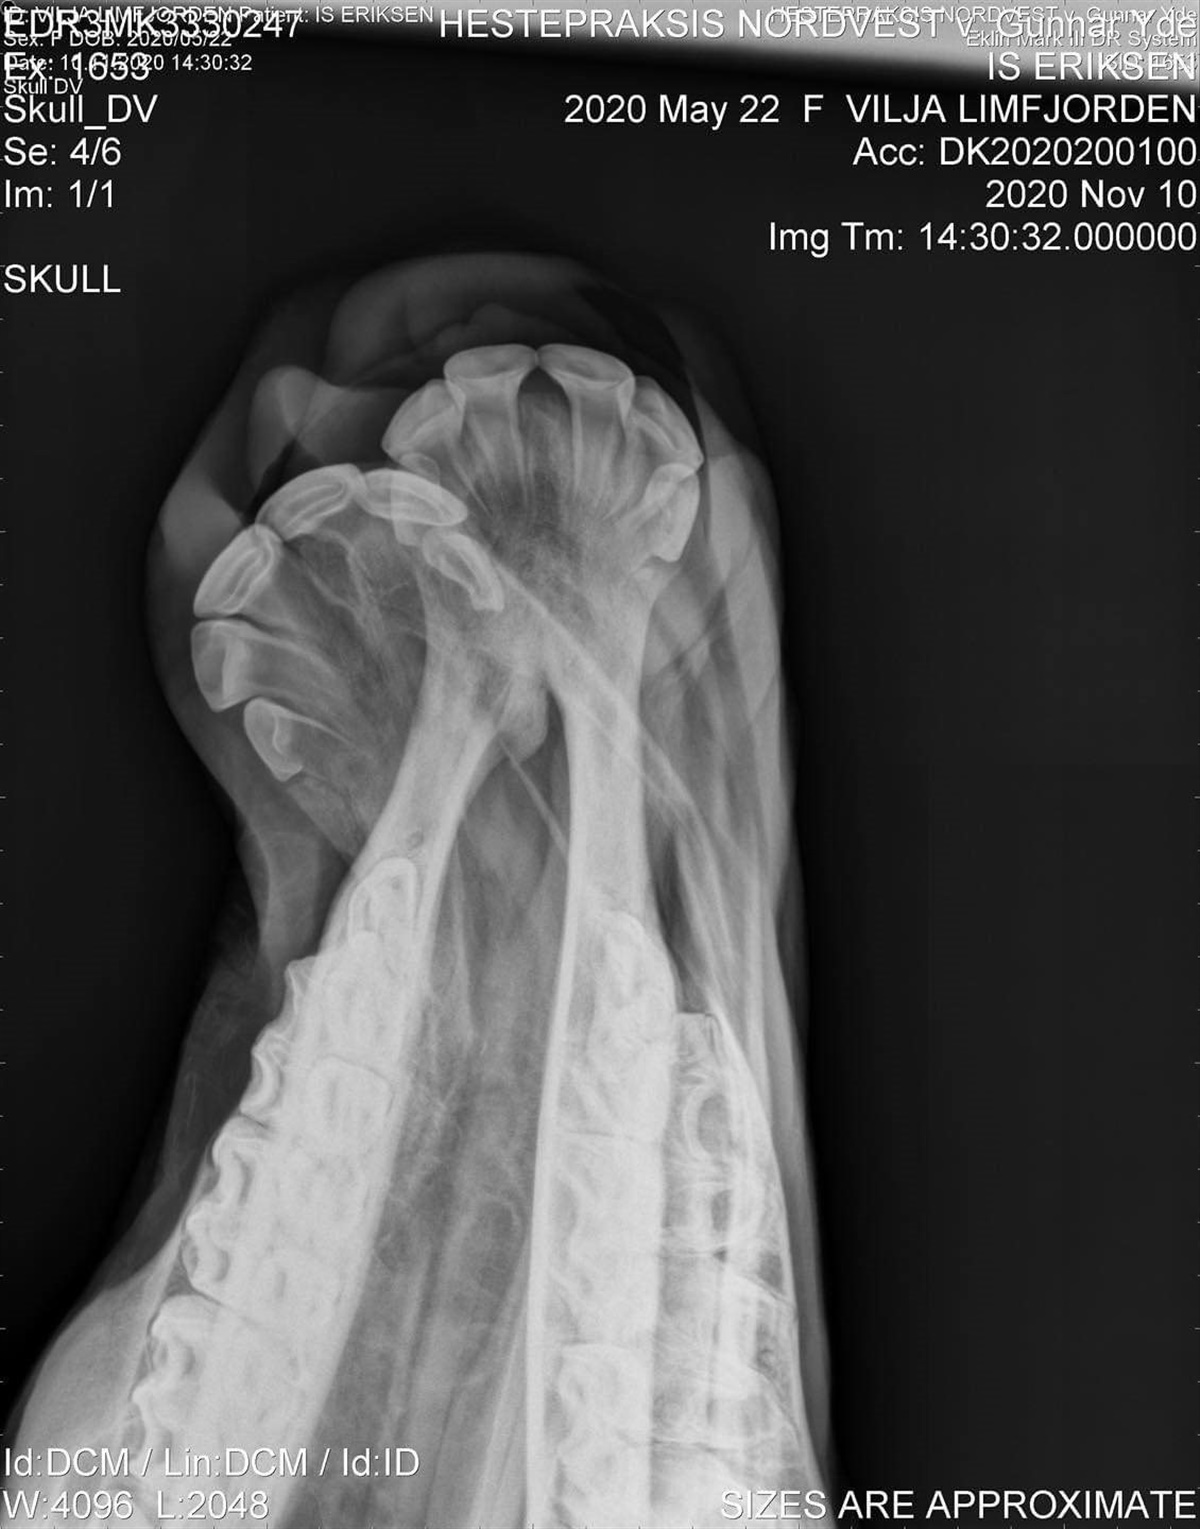

Islænderføllet Vilja blev født med skæv mule og lidelsen Wry Nose. Ofte vil man nok opgive et sådan føl, men ejerne af hoppeføllet har besluttet, at hun skal have en chance, og derfor er hun blevet opereret i håb om, at hun kan få et godt liv

Lidelsen, som det søde islænderføl Vilja fra Stutteri Limfjorden på Mors er født med, kan forekomme hos både køer, lamaer og heste, og man ved ikke præcis hvad det skyldes. Det formodes dog, at det kan skyldes en dårlig placering i livmoderen, som dermed forårsager skaden.

Christina ved ikke præcis hvad dyrlægerne har gjort, men Viljas mule er blevet rettet op, og hun står pt. med skinner og skruer, som skal holde det hele på plads.